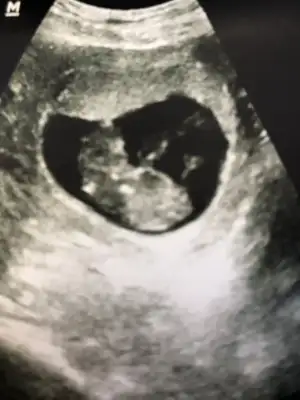

Merhabalar. Beş haftalıkken yuvarlak bir kesenin tam solundaydı ama 7 haftalıkken görüntü böyle ortada çıktı. Cinsiyet tahmini yapılabilir mi bundan da?

• 00A39E87-DFC6-4B87-A8CD-CE4AC30E65B5.webp

00A39E87-DFC6-4B87-A8CD-CE4AC30E65B5.webp

66,8 KB · Görüntüleme: 96